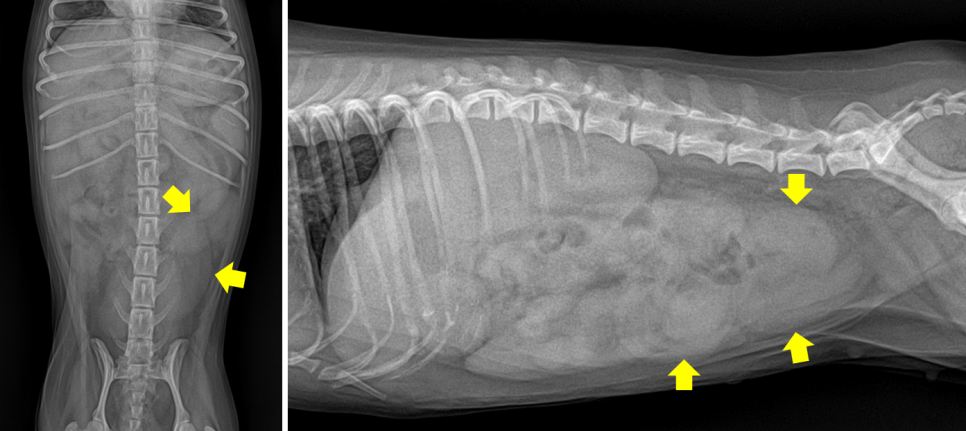

9살의 N씨가 기운이 없는 증상으로 내원했습니다.생식기에서 고름이 나오고 있었어요. 중성화 수술이 되어 있지 않은 환자였기 때문에 화상 검사를 통해 자궁의 확장을 확인했습니다.

(왼쪽) 엑스레이: 확장된 자궁/(오른쪽) 초음파: 두꺼워진 자궁벽과 농성 삼출물

엑스레이 검사로 자궁의 확장을 확인하고 초음파 검사로 두꺼워진 자궁 벽과 그 안에 막혀 있는 고름을 확인했습니다.N씨는 곧바로 응급 수술을 실시했습니다.서울앤탑 동물병원에서는 분리된 2개의 수술실에서 신속하고 안전하게 수술이 진행됩니다.